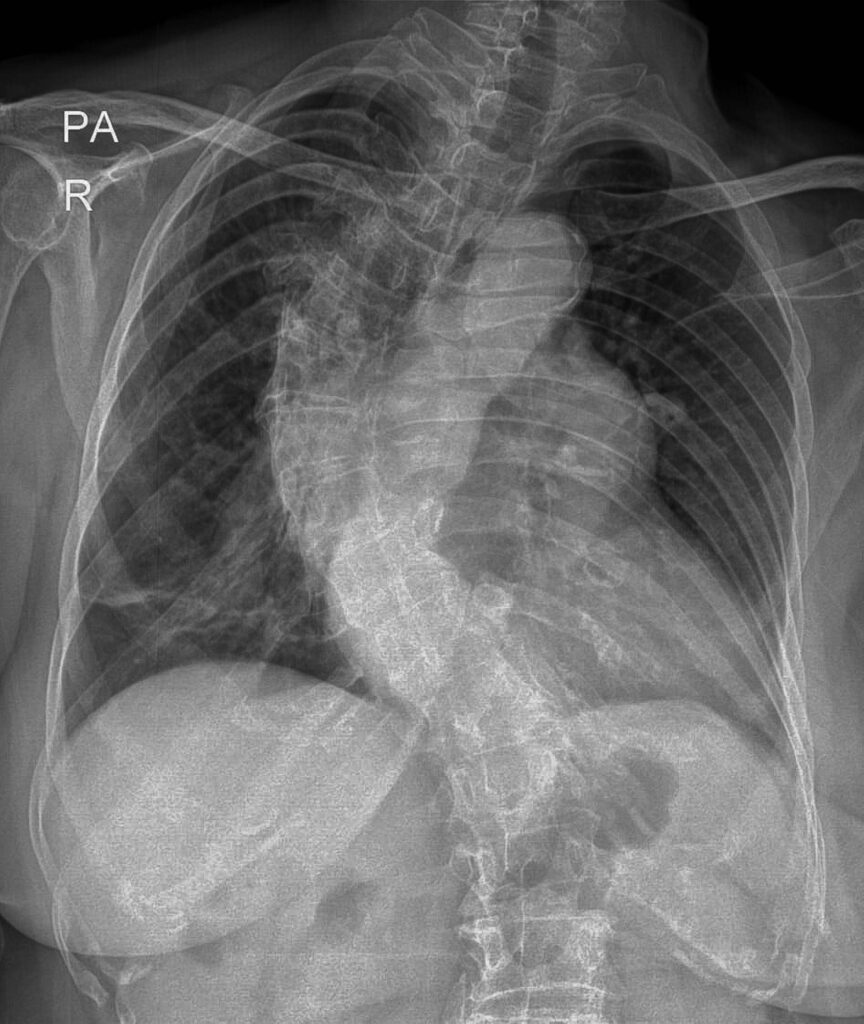

Read MoreCould It Be A Restrictive Lung Disorder?

Posted on March 21, 2025Restrictive lung disorders are those that cause difficulty in taking air inside the lungs. Restrictive disorders could include a neuromuscular disorder, obesity, or even scoliosis. If you have a hard time taking a deep, refreshing breath, give us a call at (239)-574-2644....